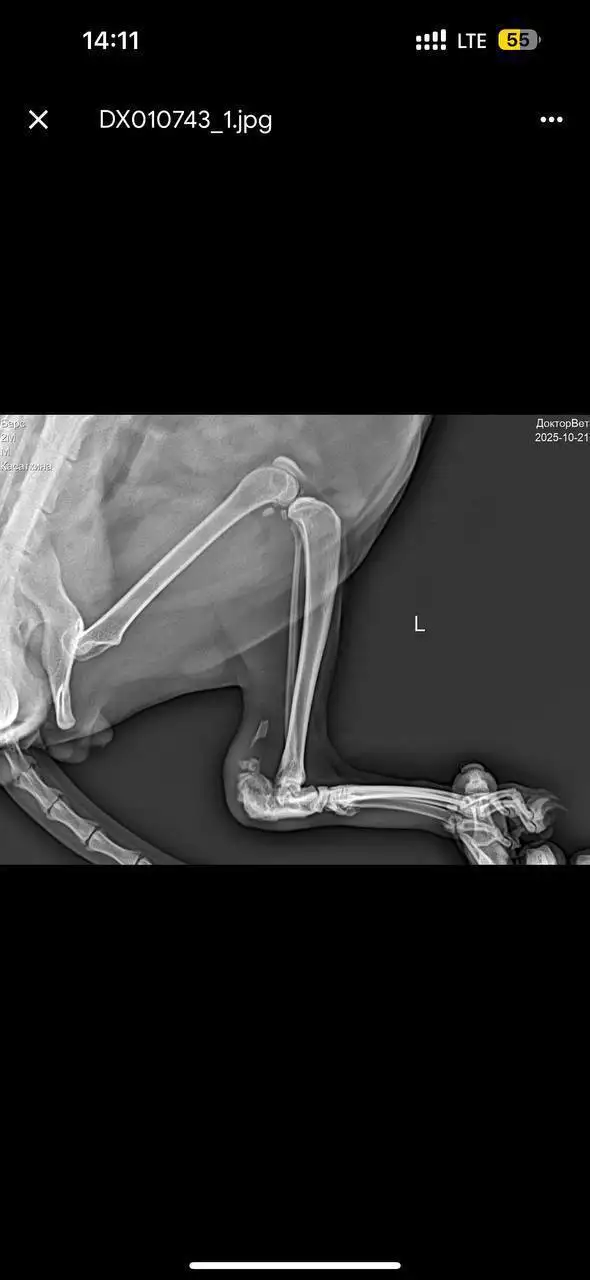

Сбор средств на лечение кота Барса

Помогите собрать средства на процедуру для кота Барса в ветклинику. Кот продолжает лечение у реабилитолога, нужна следующая процедура. Спасибо каждому, кто помогает нашему Барсу. Ему реально становится лучше, и это благодаря вам. Мы идём дальше и не сдаёмся.